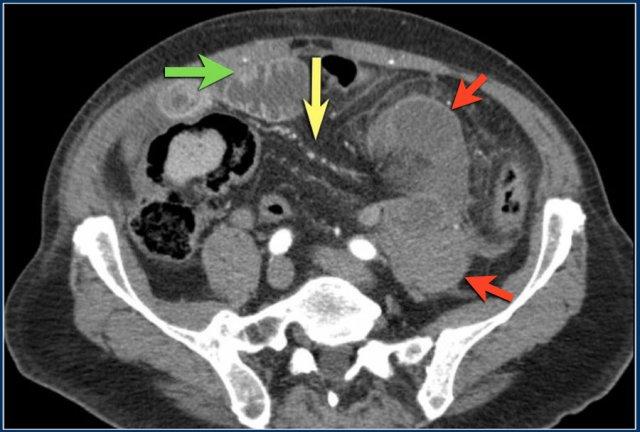

Đây là hình ảnh bệnh nhân thiếu máu cục bộ ruột do huyết khối tĩnh mạch mạc treo tràng trên – SMV (mũi tên đỏ).

Lưu ý tình trạng ứ máu tĩnh mạch trong mạc treo ruột (mũi tên vàng).

Đây là một bệnh nhân khác bị thiếu máu cục bộ một đoạn dài ruột non do tắc ruột quai kín.

Một đặc điểm hình ảnh quan trọng của tắc ruột quai kín là hình ảnh các quai ruột non giãn xếp theo kiểu nan hoa bánh xe với các mạch máu mạc treo hội tụ về một điểm trung tâm.

Các dấu hiệu thiếu máu cục bộ trong tắc ruột quai kín tương tự như ở các bệnh nhân có nguyên nhân thiếu máu cục bộ mạc treo khác:

- Dày thành ruột

- Phù nề mạc treo ruột

- Cổ trướng

- Sự ngấm thuốc của thành ruột trong thiếu máu cục bộ có thể bình thường, tăng do hiện tượng tái tưới máu, hoặc giảm/mất ngấm thuốc như trong trường hợp này.